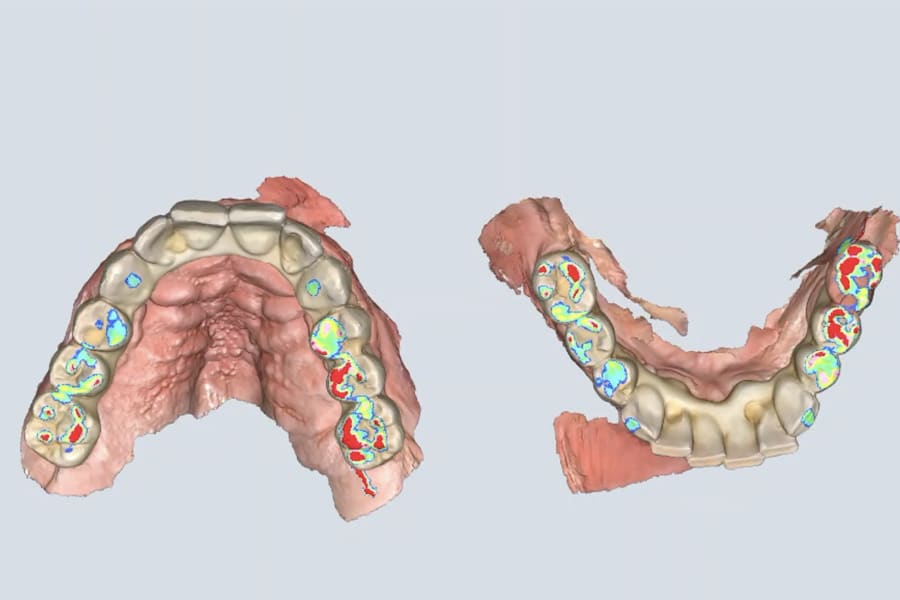

At the definitive phase, scan bodies were connected, and digital impressions were made. A passive-fit verification jig was fabricated by splinting implant analogs with resin, then sectioning and re-luting to relieve shrinkage stress (Figure 21). The jig confirmed accuracy intraorally and on the master model, ensuring a strain-free framework.

Occlusion was once again validated using jaw-motion tracking, confirming harmony with functional dynamics (Figure 28). The definitive prostheses were delivered as screw-retained restorations, achieving esthetic integration, functional stability, and patient satisfaction (Figure 29 and Figure 30).